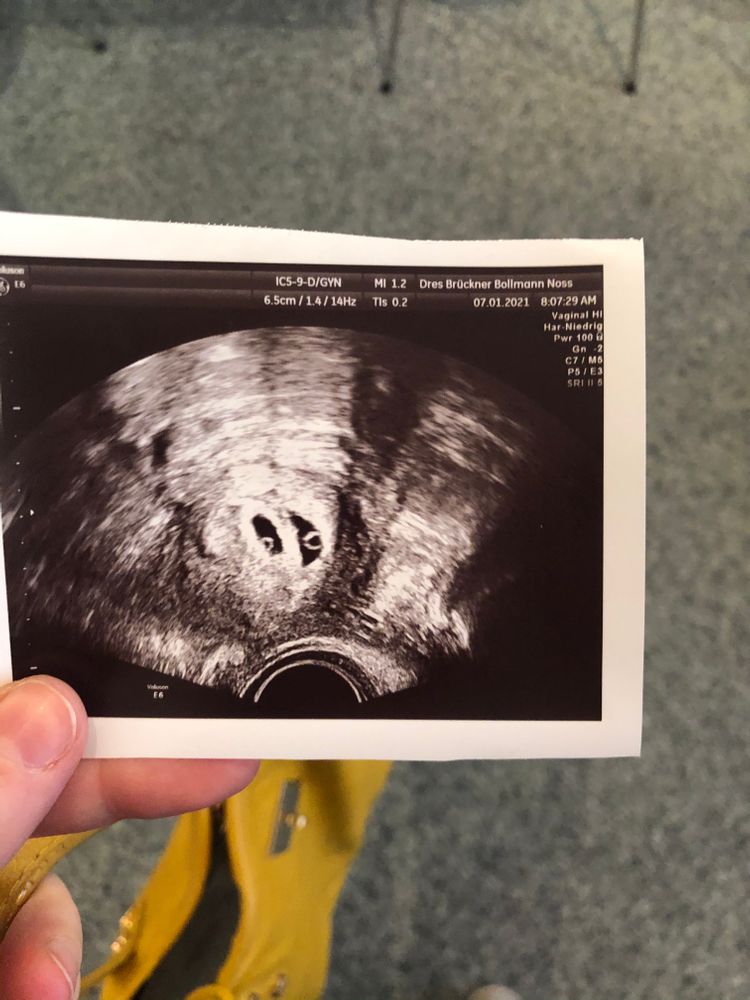

Беременность 6+0

Я буду мамой двойняшек! Принимаем в наши рядыВсем привет! Я в группе новенькая, только на прошлой неделе была на первом узи - нашли двух бусинок, фото прилагаю 🍀🍀 девочки, все было бы хорошо, но вчера у меня вышла темная кровь-слизь, немного, но яичник болит до сих пор. Кровь вышла, только когда была в туалете и сразу остановилась. У меня это уже второй раз, когда кровит. Может это быть старая кровь, как на месячные? Очень надеюсь, что детки в порядке, на узи иду только в конце недели.

Фото прям огонь!!! Поздравляю!!! От двойняшек двойняшкам огромный привет !!! Легкой беременности, бетонной шейки!!!